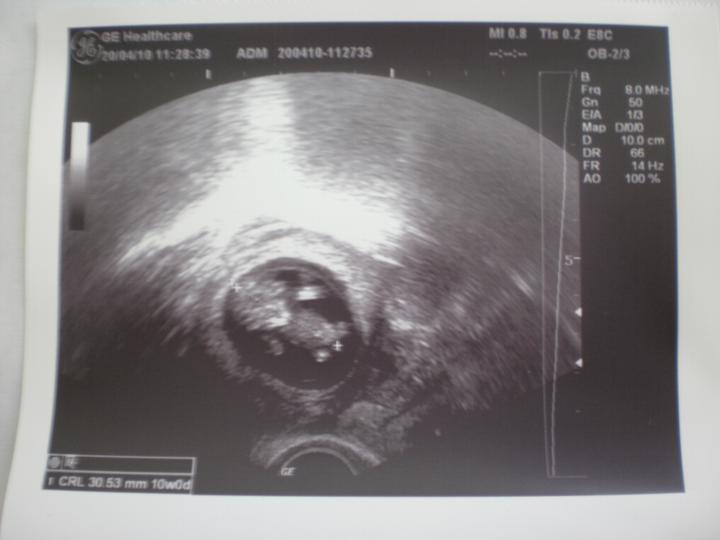

Dnešní kontrola u lékaře dopadla skvěle. Už jsme obdrželi těhotenskou knížku a zjistili jsme, že jsme v 10+0 týdnu a termín porodu máme 12.11.2010. Krevní testy v naprostém pořádku :o)